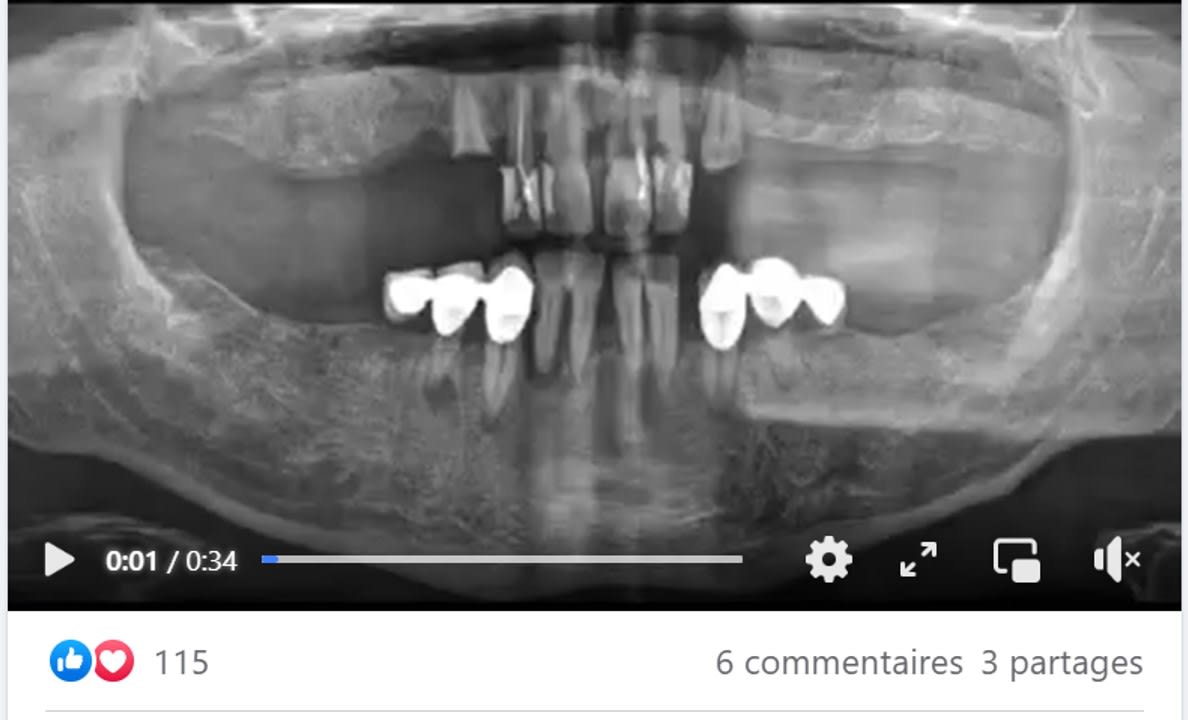

Un exemple d'un cas plébiscité pourtant lacunaire

j'y vois des greffes de sinus en vu d'une MCI se qui implique environ 6 mois d'attente avec un antago précaire.